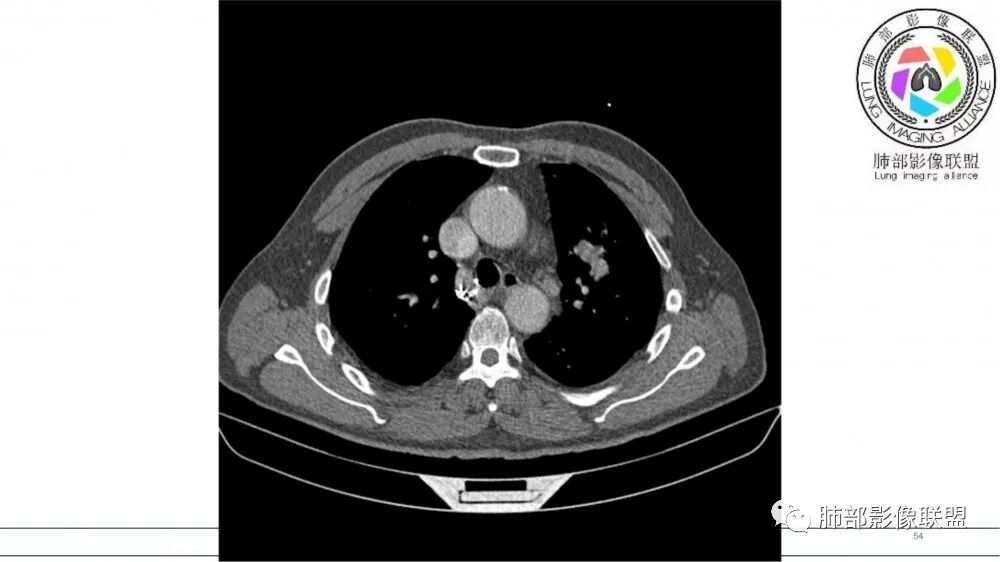

左肺上叶前段支气管内铸形生长软组织影,增强后均匀强化,远侧见斑片状磨玻璃影。考虑恶性病变,粘表?粘液腺?

老年男性,左肺上叶前段支气管内铸形阴影,增强后病灶不均匀强化,内部有坏死?远端可见斑片状阴影(阻塞性肺炎)。考虑恶性病变,老年人,鳞?类癌?粘表不能排除。

男,70岁,吸烟史,咳嗽,胸闷憋气一个月,左肺上叶不规则形软组织密度影,病灶沿支气管走形,周围见粟粒及棉絮样稍高密度影,增强扫描病灶内见少许坏死,考虑鳞癌可能,鉴别结核。

老年男性,肺气肿,吸烟史,左肺上支气管腔内铸型高密度影,呈指套状,远端多发树芽,增强不均匀强化,考虑鳞癌,鉴别小细胞癌

B3指套征,常规不是鳞癌就是ABPA,有强化丶血管造影征,倾向于鳞癌

指套征,扩张支气管内软组织强化,远侧肺野阻塞性炎,纵隔、左肺门肿大淋巴结;老年男性,吸烟,考虑鳞癌,鉴别小

指套征:是影像征象,胸部平片表现为手指状密度增高影,以肺门为中心呈放射状分布,CT显示扩张支气管内低密度黏液栓形成或实性病变,呈管状、树枝状或卵圆形密度增高影;支气管扩张伴近端梗阻时,扩张支气管内部黏液分泌物不能排出而形成。可以伴随远端空气潴留征、阻塞性炎症。